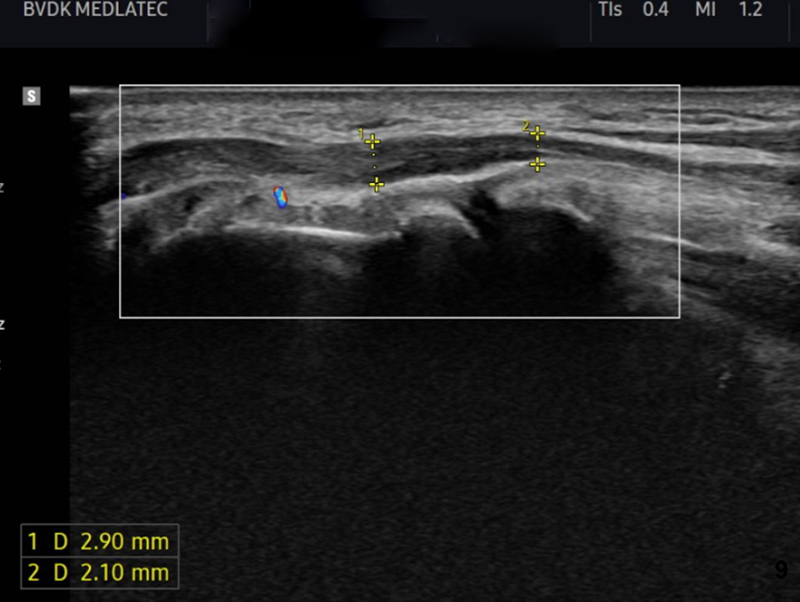

Kết quả điện cơ cho thấy, tốc độ dẫn truyền vận động và cảm giác của dây thần kinh trụ bên trái bị giảm. Siêu âm thần kinh trụ ghi nhận tăng diện tích dây thần kinh trụ đoạn trước đường hầm xương trụ - dấu hiệu đặc trưng của chèn ép thần kinh.

Siêu âm cho thấy dây thần kinh trụ có dấu hiệu bị chèn ép

Từ những kết quả lâm sàng và cận lâm sàng, bác sĩ kết luận, ông Q. mắc hội chứng đường hầm thần kinh trụ tại khớp khuỷu tay trái - một bệnh lý có thể ảnh hưởng đến vận động bàn tay nếu không điều trị kịp thời.